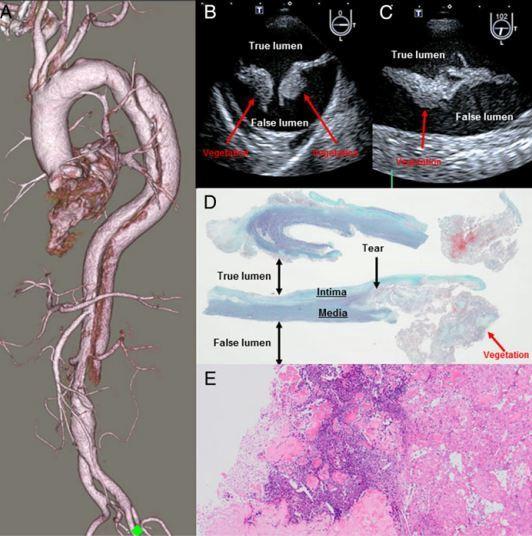

患者,男,74 歲,因“持續高熱 13 天”入院,既往無免疫性疾病。當地醫院通過腦脊液及血培養診斷為鏈球菌性腦膜炎。入院 CT 檢查提示

DeBakey III 型主動脈夾層(圖 A),經食道超聲心動圖檢查顯示主動脈夾層入口內膜內有一明顯贅生物(圖 B 和

C)。無瓣膜性心內膜炎或任何先天性心臟病所致心內膜炎證據。

主動脈夾層入口組織學檢查 Elastica-Goldner 染色顯示贅生物位于內膜和中膜撕裂處(圖 D),贅生物 HE

染色提示中性粒細胞浸潤和嗜堿性壞死物質(圖 E)。主動脈檢查未發現細菌,主動脈組織標本培養結果也為陰性。另外,夾層撕裂部位可見動脈粥樣硬化病變。

圖:CT、心臟超聲和組織學檢查結果